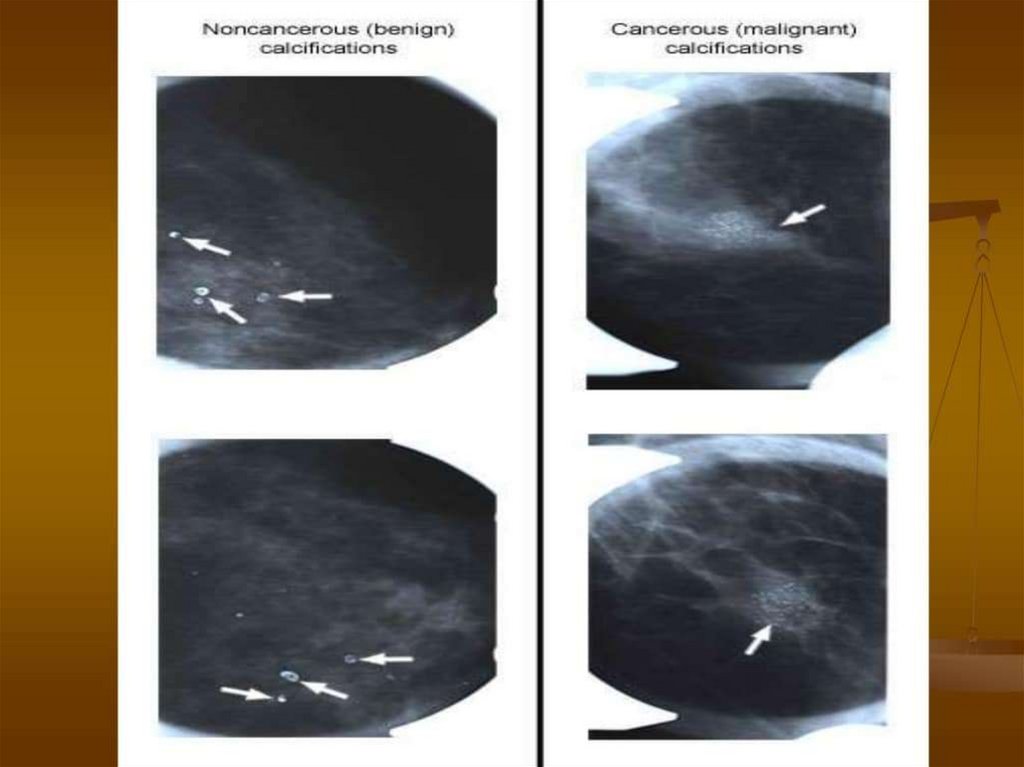

Benign Breast Disease